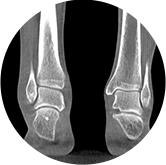

支持双腿或双侧髋关节扫描 | 方便对比,降低漏诊误诊

FOV 250mm

FOV 350mm